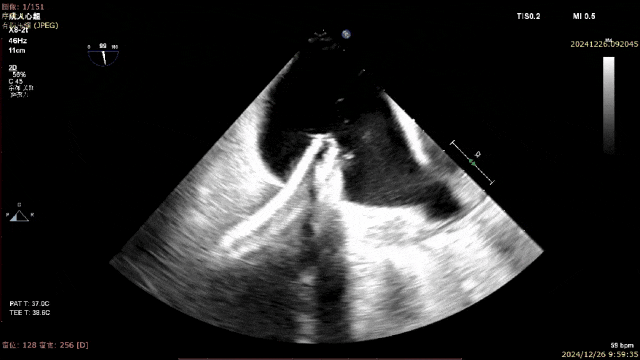

术中导引鞘和二尖瓣夹植入

二尖瓣夹释放后评估